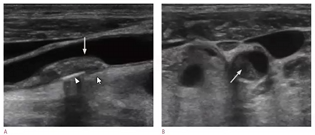

Note the double white line in the arterial lumen. what condition is suspected in this B-mode image?

carotid artery dissection

Patient is 38 y/o female with stroke like symptoms. No risk factors or medical history. You take this image of distal ICA.

1. What is the sonographic description of distal ICA?

2. What does this indicate or what is possible diagnosis?

3. Is this related to atherosclerosis?

4. What is important in patient clinical presentation for possible diagnosis?

5. Which other vessels most likely impacted by this?

string of pearls

FMD

No (congenital abnormality)

young female

Renal artery’s